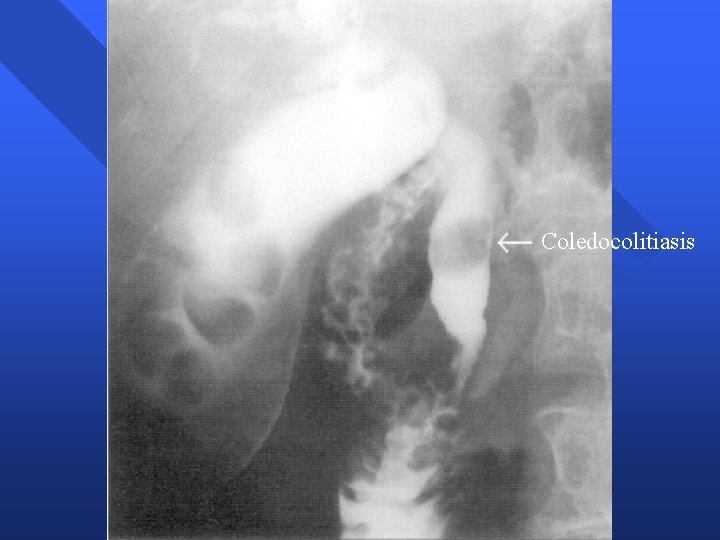

Coledocolitiasis n Clínica – Cólico biliar – Ictericia obstructiva – Colangitis aguda – Pancreatitis biliar n Situaciones clínicas – Con vesícula in situ – Postcolecistectomía

Coledocolitiasis